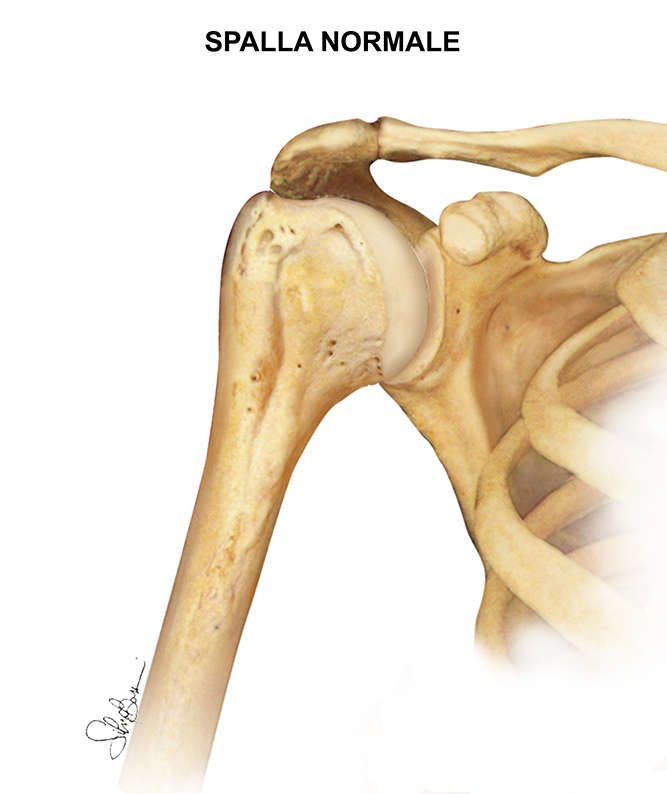

L’articolazione della spalla è composta da tre ossa: l’omero, la scapola e la clavicola le quali a loro volta si uniscono a formare 2 distinte articolazioni: acromion-clavicolare e gleno-omerale. Le superfici articolari sono ricoperte da cartilagine, una sostanza liscia che protegge le ossa e consente loro di muoversi con facilità. Inoltre un migliore scorrimento delle superfici articolari è garantito dalla membrana sinoviale, la quale ricoprendo parte delle superfici articolari, produce un liquido in grado di lubrificare la cartilagine ed elimina quasi ogni attrito nella spalla.

La stabilità e il sostegno dell’articolazione invece è garantita dai muscoli e dai tendini che circondano la spalla stessa.

Il simultaneo lavoro di tutte queste strutture consente alla spalla di ruotare attraverso una maggiore gamma di movimento rispetto a qualsiasi altra articolazione del corpo.